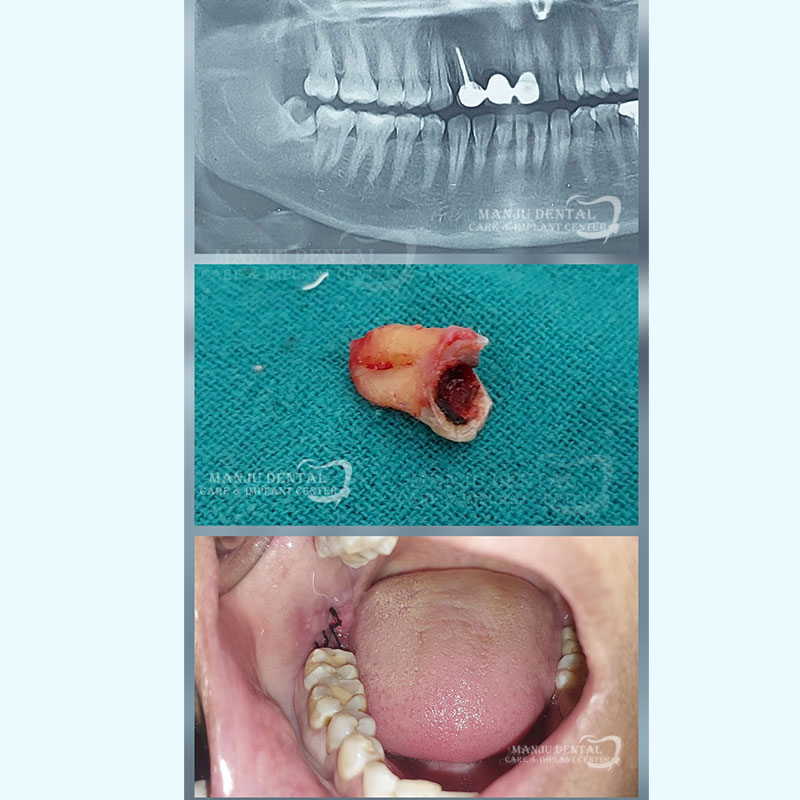

Surgical Extraction of Impacted Lower Wisdom Tooth

Root amputation and hemisection.

A root amputation requires the surgical removal of one root if a tooth is multi-rooted. If one or more tooth roots become infected or there is significant bone loss around the tooth hemisection is done. During the procedure half of the tooth is removed leaving a serviceable one-rooted tooth.